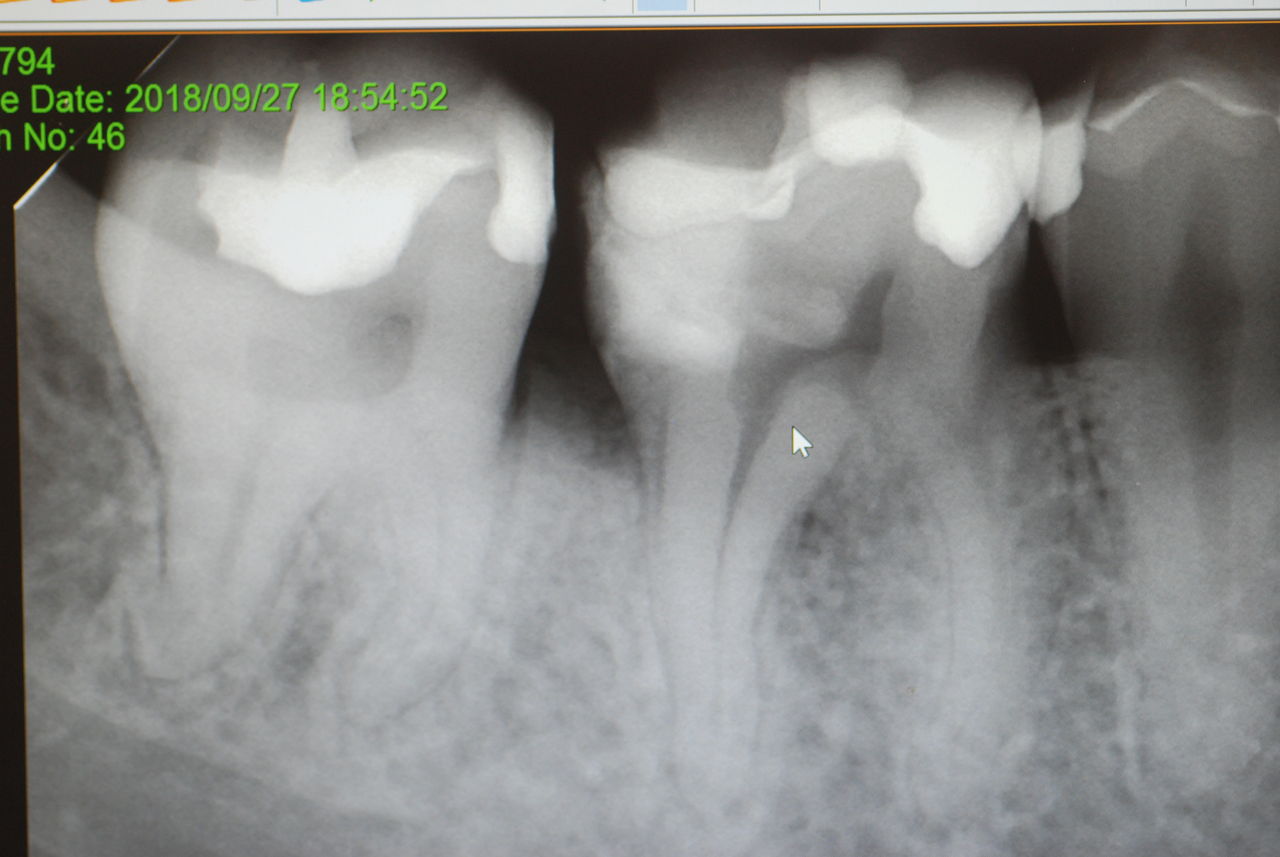

2、67才、女性、主訴は噛みあわせがおかしい。

矯正している。左の上下の6才大臼歯を保険の金属冠から都内の某所でジルコニアという硬いセラミック?冠に変えてからおかしくなっていったそうです。担当の歯科医師は削ったりしてどちらの歯も当たっていないぐらい削っているに違和感が取れないという主訴です。兵庫県の先生からの相談でした。

ここでも議論がわかずに、私も多分そうではないかと考えていたのですが、歯科心身症の方のようです。心身症というには、普通の方ですが、歯の部分の違和感や噛みあわせ云々と言われる方の殆どは、歯の治療に問題がなければ、歯科での治療に伴う異常な感覚がぬけなくなるという方がいるのです。